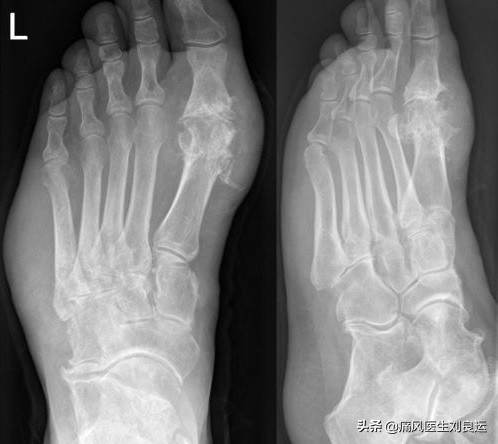

X光下左脚痛风